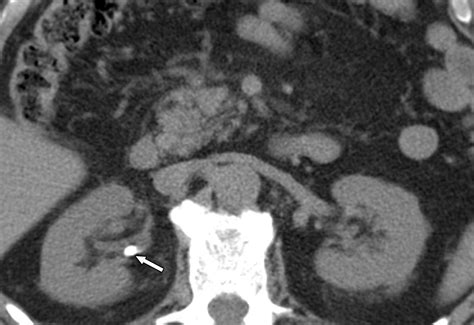

A kidney stone, or renal calculus, is a hard, crystalline deposit made of minerals and salts that form inside your kidneys. When a medical professional identifies a 3 mm kidney stone, they are describing its diameter. To put this into perspective, 3 millimeters is roughly the size of a grain of sand or a very small seed. Although it sounds minuscule, the ureters—the tubes connecting your kidneys to your bladder—are narrow and delicate, making the passage of even a tiny, jagged object feel disproportionately painful.